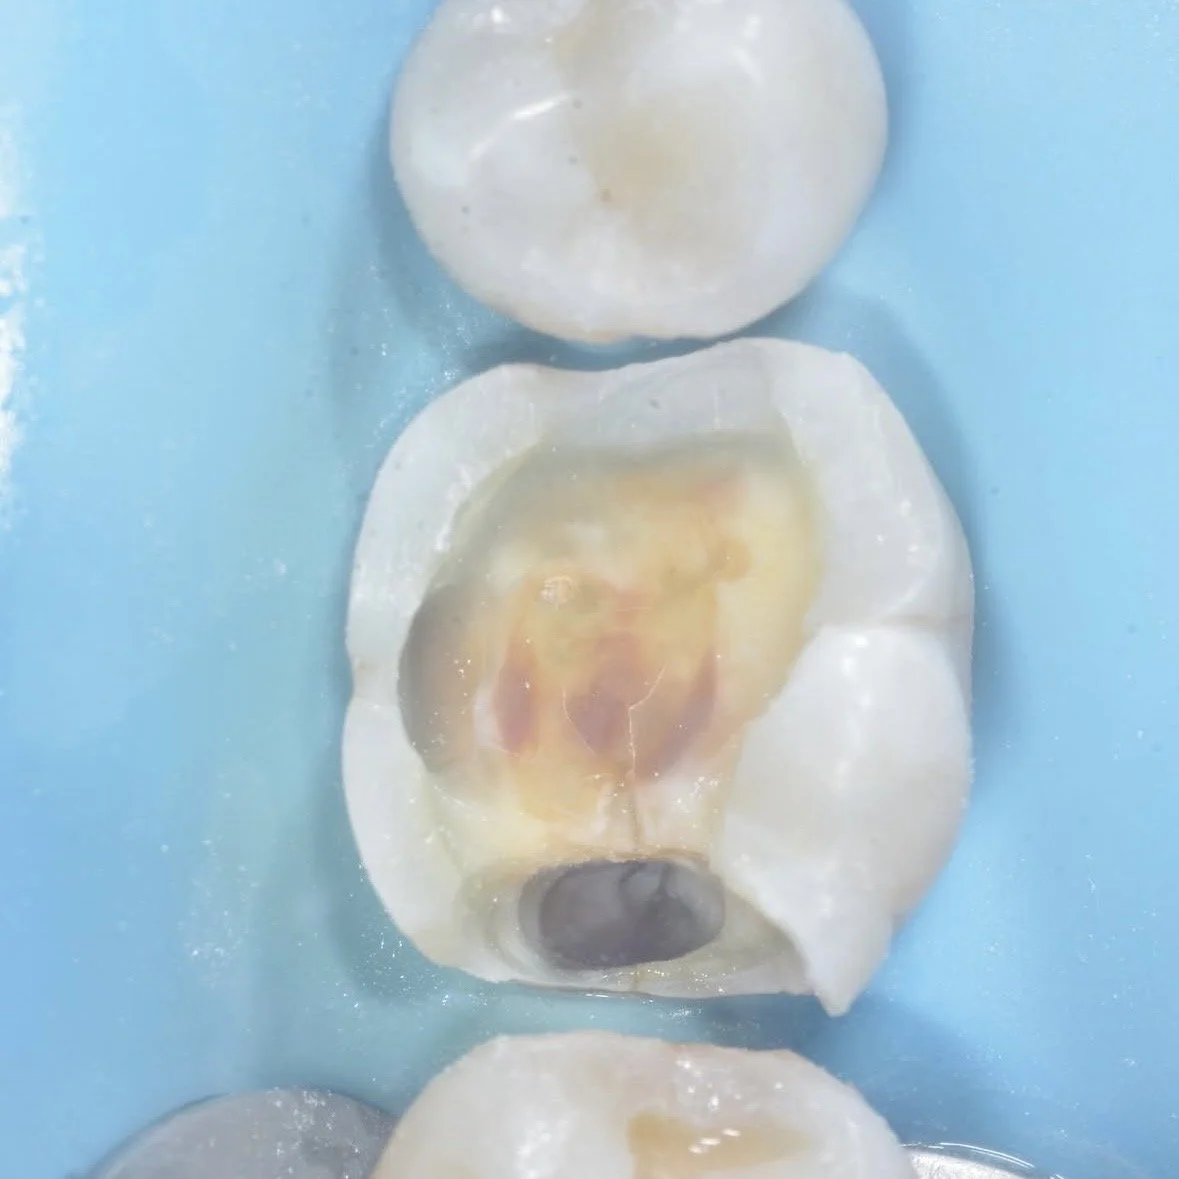

A crack is visible in this case, stained pink from caries detector dye. In this case the crack was removed fully around, but not into, the center of the tooth for two reasons:

1. The tooth’s nerve (pulp) lives in the center of the tooth. Drilling into this area and exposing the pulp can lead to infection and necrosis, requiring root canal therapy.

2. The most important bonding area is around the pulp. Think of a dome — it is very strong despite being hollow on the inside. A tooth functions in the same way around the pulp, so a stable, crack-free foundation in this area is important for a long-lasting restoration.